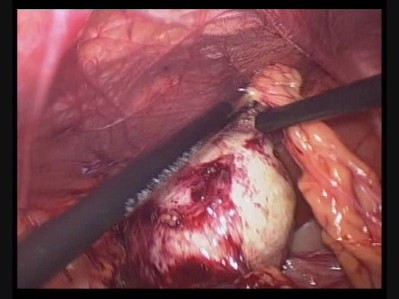

Pooja Priya chronic ovarian torsion2min 25 sec October 2, 2014 399 × 299 SURGERIES PERFORMED Like Loading...